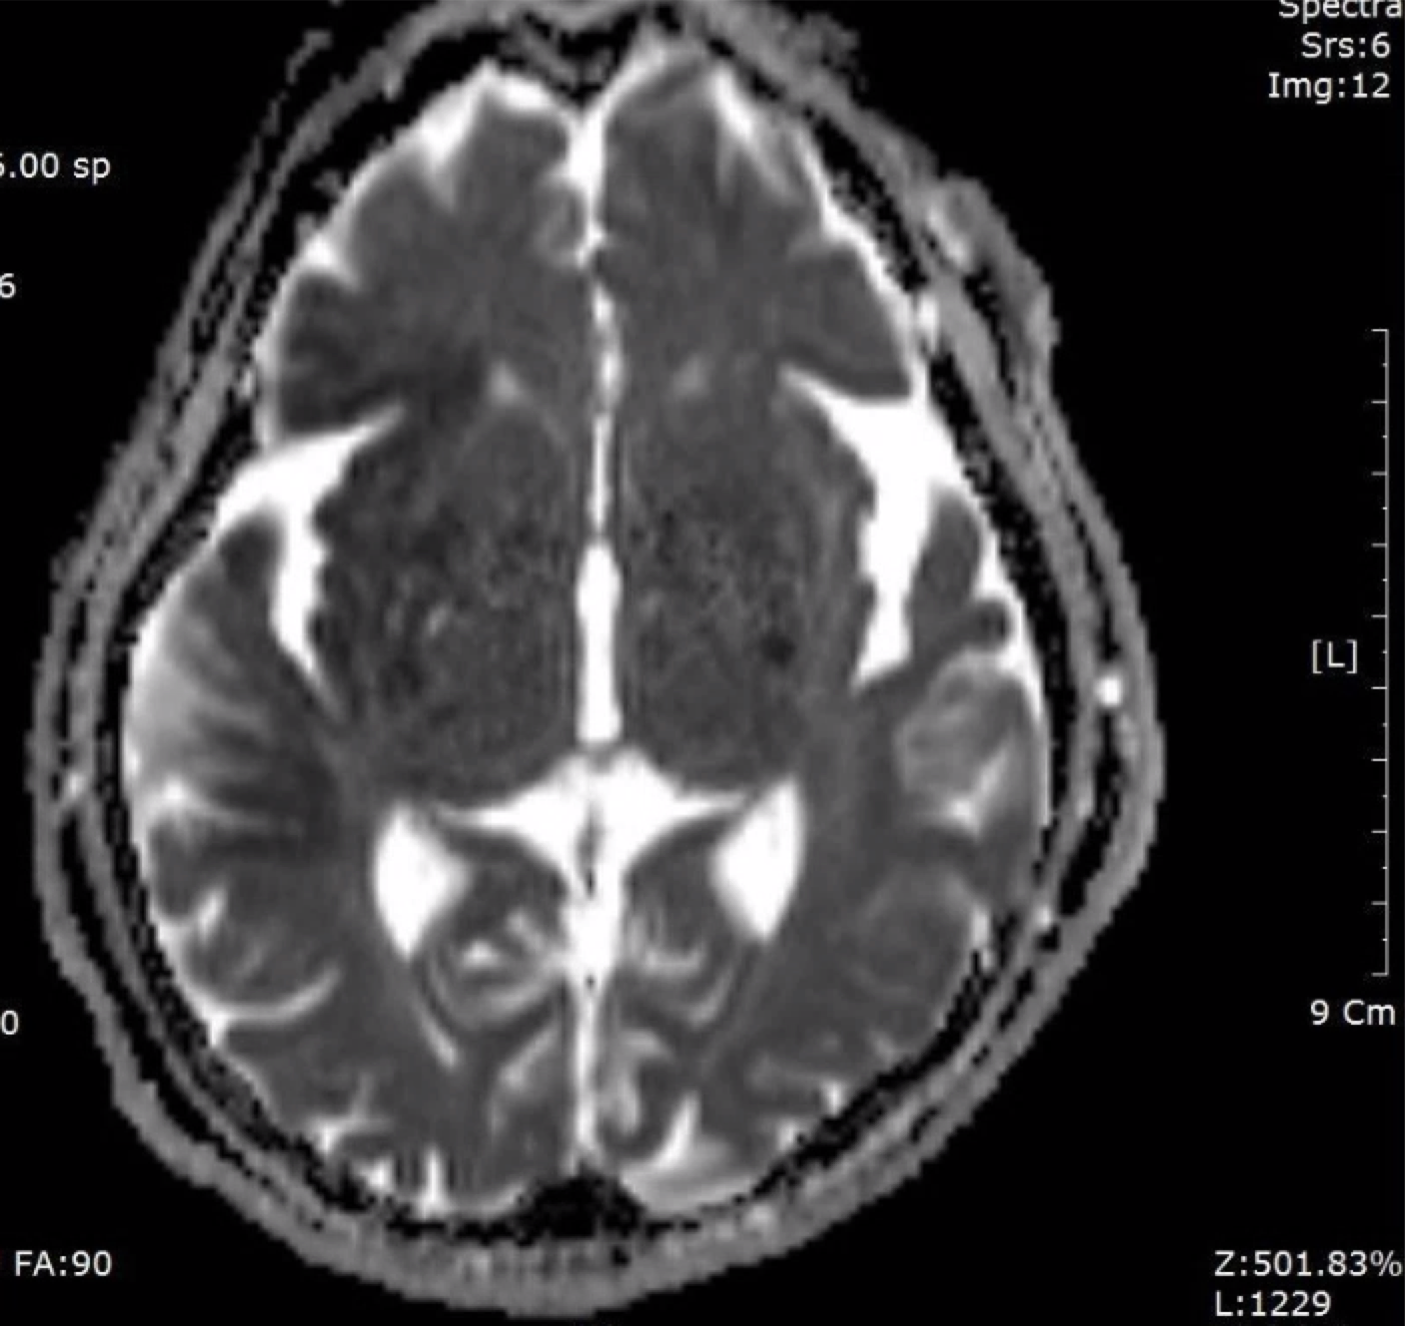

F/73

left hemiplegia due to cerebral infarction 2016.9.16.

cognitive impairment

vascular dementia